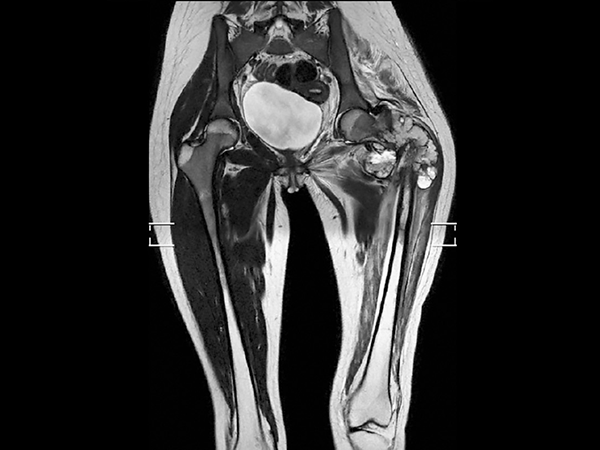

Preoperative MRI in this young girl demonstrates the large tumor with a necrotic component and areas of fluid. The tumor extends down into proximal part of femur. Edema is seen along the femoral shaft down to the knee and in the gluteal muscle. T2W mDIXON TSE in-phase and water images show the superb fat suppression of mDIXON TSE. The two-station MobiView also demonstrates the high quality mDIXON TSE fat suppression over large region and both images with and without fast suppression are obtained in about half the time needed for conventional scans.

Coronal T2w TSE mDIXON (water only)